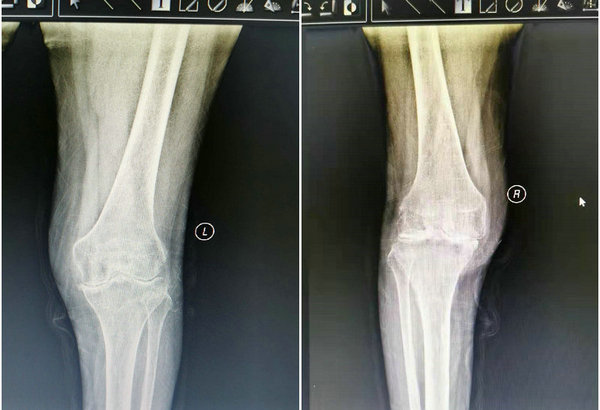

术前双膝影像检查图